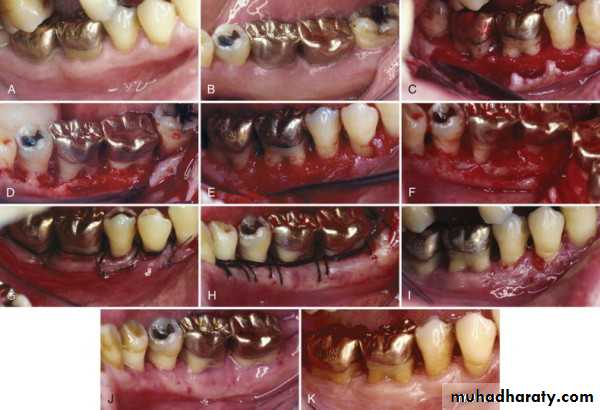

Replaced flap(un repositioned flap , Nondisplaced flaps)

Currently, it is the most commonlyperformed type of periodontal surgery.•It differs from the modified Widman flap in that the soft tissue pocket wall is removd with the initial incision; thus it may be considered an internal bevel gingivect, Initial incision through marginal gingiva to the crest of the alveolar. Knife should be parallel to the long axis of the tooth. The distance between the surface of the tooth and the incision depends on the depth of the pocket .Be sure in removing all the Sulcular epithelium from the margin of the incision, vertical incision can be done if needed.

The flap is then reflected, and all the tissue around and between the teeth should be removed. Thorough root planning and cleaning of the infra-bony pocket can be performed.

The flap margins are now sutured again and the area can then covered with periodontal pack.

Apically repositioned flap

It can be used for both pocket eradication as well as widening the zone of attached gingiva. •It can be a full thickness (mucoperiosteal) or a split thickness (mucosal) flap. The initial incision is performed as before, but preserves most of the attached gingiva, by locating the incision as near to tooth surface as possible. Vertical incision must be extended to the muco buccal junction. After thorough root planning the flap is then undermined and push apical to the level of the alveolar bone. On the palatal side, the flap can not be pushed apically, but the margin is undermined before suturing. The flap is sutured in a way that its margin is now located apical to its original position.ADVANTAGES:

•Eliminates periodontal pocket.

•Preserves attached gingiva and increases its width. •Establishes gingival morphology facilitating good hygiene. •Ensures healthy root surface necessary for the biologic width on alveolar margin and lengthened clinical crown.